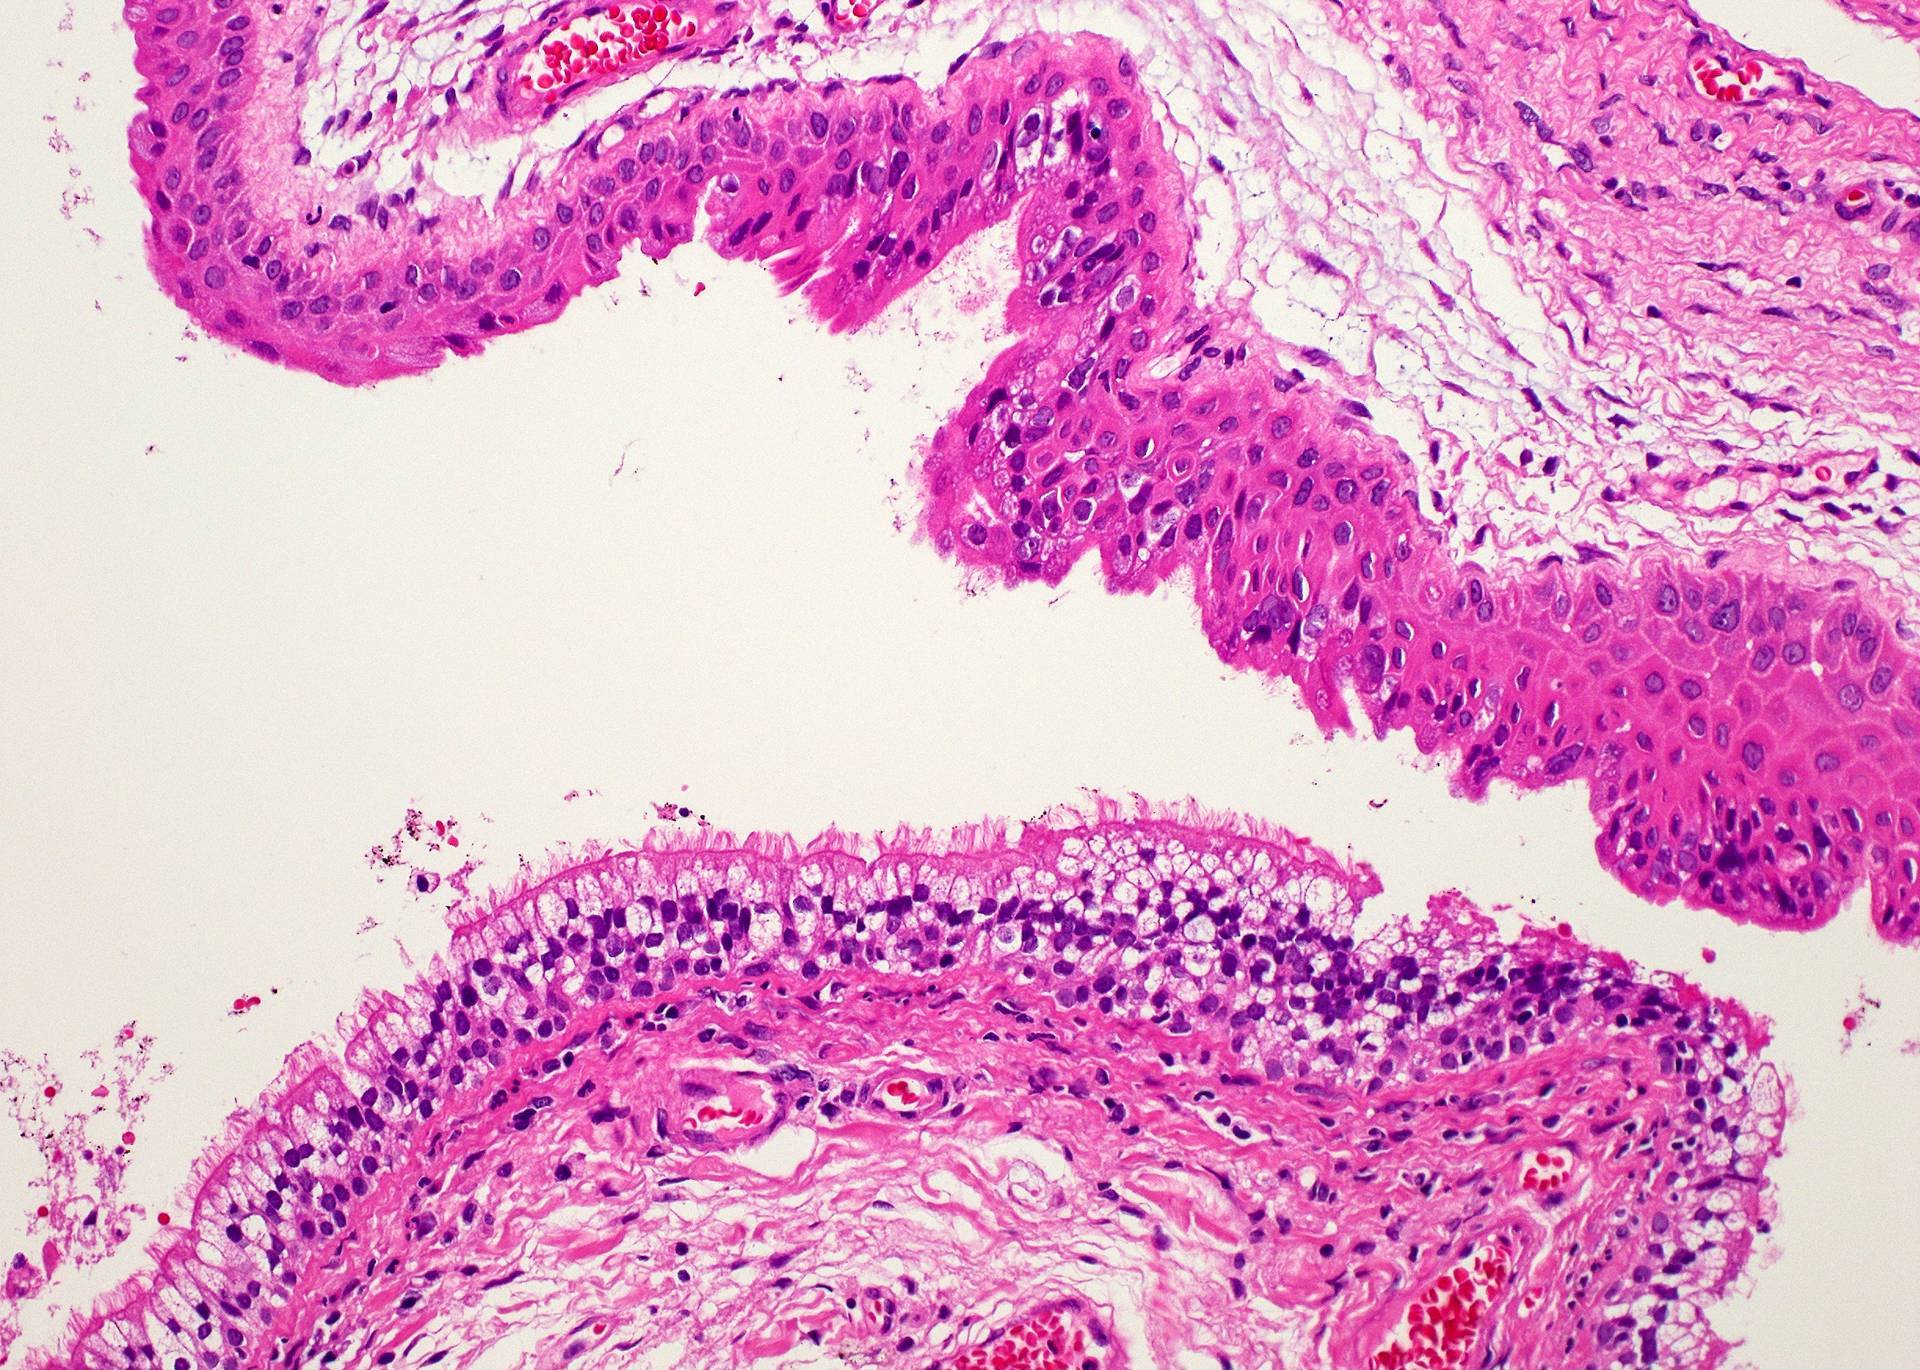

Microscopic (histologic) description

- Type of epithelial lining varies by site, and combinations of the types below can be seen in a single cyst (Head Neck Pathol 2013;7:50):

- Ciliated pseudostratified columnar (respiratory) epithelium in lower neck, perhaps due to its close proximity to upper respiratory tract

- Nonkeratinizing squamous epithelium in higher neck (near tongue and foramen cecum), also can be of metaplastic origin in inflammatory settings

- Stratified cuboidal epithelium at level of hyoid bone

- Very often the cyst is denuded of epithelium, at least focally, which reflects epithelial damage by inflammation

- Secondary inflammation is common, especially in sinus tract (J Pediatr Surg 1984;19:506):

- Intense lymphocytic infiltration, rarely arranged into lymphoid follicles

- Admixture of neutrophils (if the cyst is infected)

- Granulation tissue and fibrosis

Microscopic (histologic) images

Contributed by Andrey Bychkov, M.D., Ph.D., Mark R. Wick, M.D. and AFIP